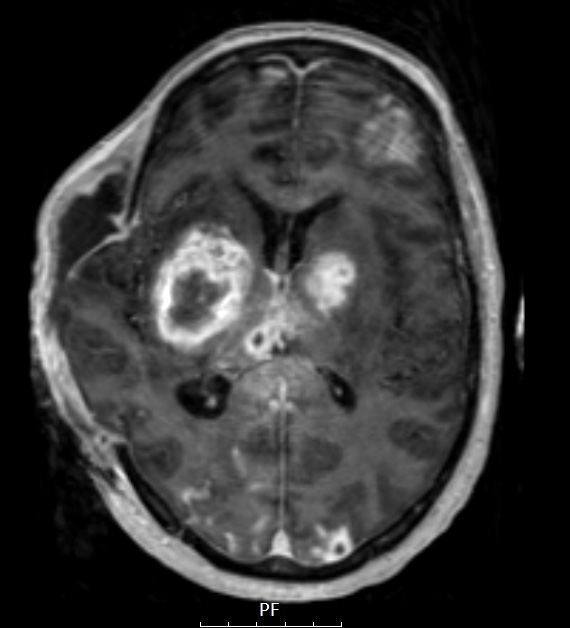

A T1 MPRAGE with contrast shows multiple enhancing lesions.